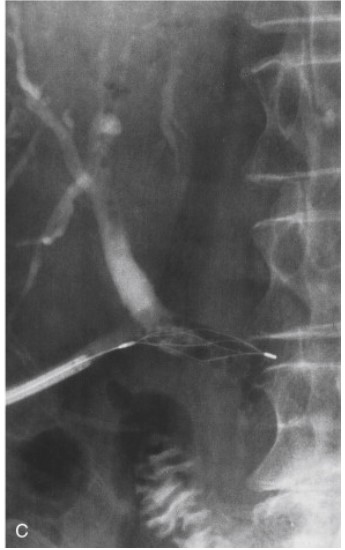

Figure 20-27. Percutaneous extraction of a retained common bile duct stone through a T-tube track. A, The T-tube has been removed and a steerable Burhenne catheter placed through the percutaneous track into the bile duct to the level of the stone (small arrow) . A basket (curved arrow) has been placed distal to the stone. B, The basket is pulled back and manipulated so that the stone (arrow) is engaged within the basket and the basket is then pulled back against the end of the Burhenne catheter. Basket, stone, and Burhenne catheter are then removed through the percutaneous track. C, There is some air present in the lower bile duct. The basket was traversed through the lower bile duct but no further stones were present. Contrast injection at the end of the procedure showed a clear bile duct.